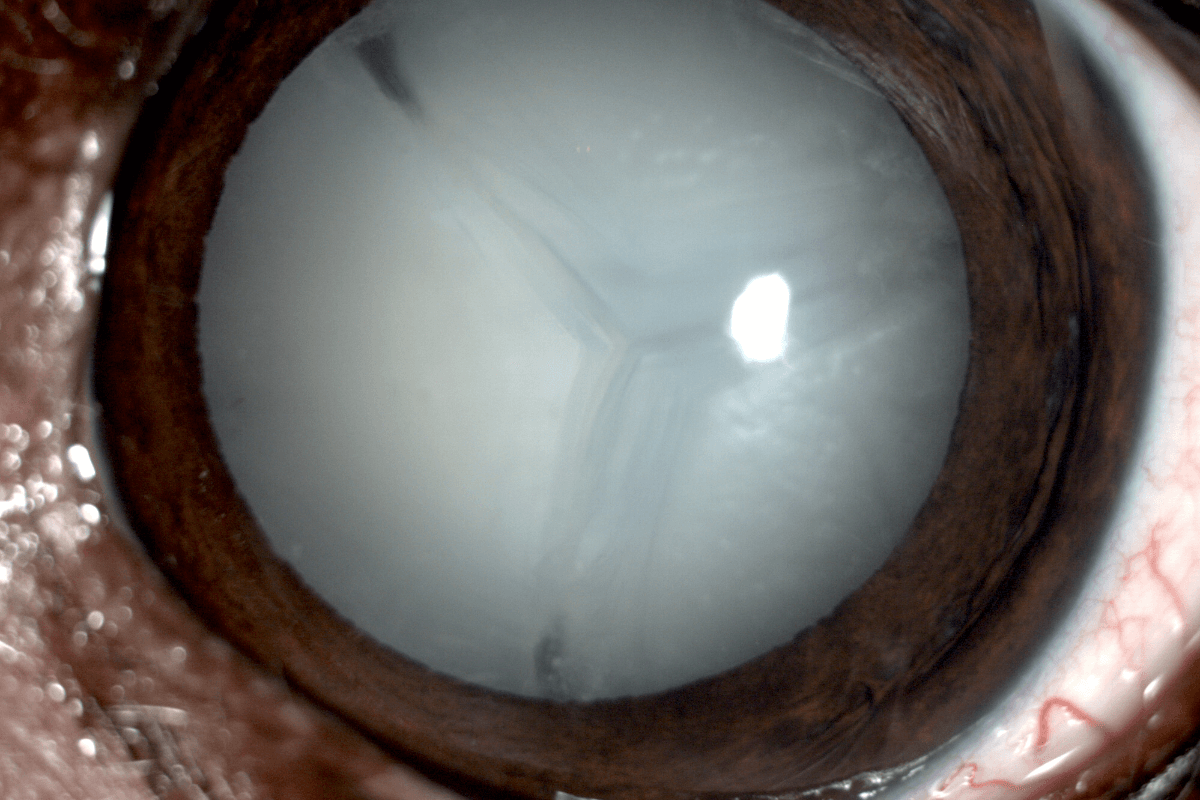

Un perro de 11 años, con diabetes y ceguera debido a una catarata asociada a su enfermedad endocrina, fue recientemente tratado por el equipo veterinario especializado en oftalmología de AniCura Ocaña Oftalmología Veterinaria. El caso despertó especial interés por la complejidad que supone intervenir a un paciente con diabetes y, al mismo tiempo, restaurar su visión de forma completa. "Se trata de un caso de gran relevancia, especialmente porque la recuperación visual fue prácticamente inmediata tras la cirugía, lo que lo convierte en un ejemplo ideal para visibilizar la importancia de la salud ocular en el Día Mundial de la Visión", explica Javier Esteban Martín, Practice Manager de AniCura Ocaña.

El diagnóstico y el plan de tratamiento se definieron tras un examen oftalmológico exhaustivo, diseñado para comprobar que la retina funcionara correctamente y maximizar las probabilidades de éxito de la cirugía. Durante la evaluación se estudiaron los reflejos fotopupilares cromáticos y acromáticos, se midió la presión intraocular, se realizó una gonioscopia para examinar el ángulo iridocorneal, y se llevó a cabo una ecografía ocular para confirmar la posición de la retina y descartar alteraciones del vítreo. Además, se realizó una electrorretinografía para verificar el correcto funcionamiento de los fotorreceptores.

Las enfermedades oculares más frecuentes en los animales de compañía suelen comprometer principalmente la superficie del ojo, generando molestias que pueden afectar a su visión y bienestar general. Entre ellas destacan las úlceras corneales1, provocadas por traumatismos, cuerpos extraños vegetales o infecciones, y las queratitis, inflamaciones de la córnea que pueden tener origen inmunológico, alérgico o infeccioso. Las cataratas representan otra de las patologías más comunes, especialmente en perros de edad avanzada o con trastornos metabólicos como la diabetes mellitus2, que alteran la transparencia del cristalino y reducen la agudeza visual.